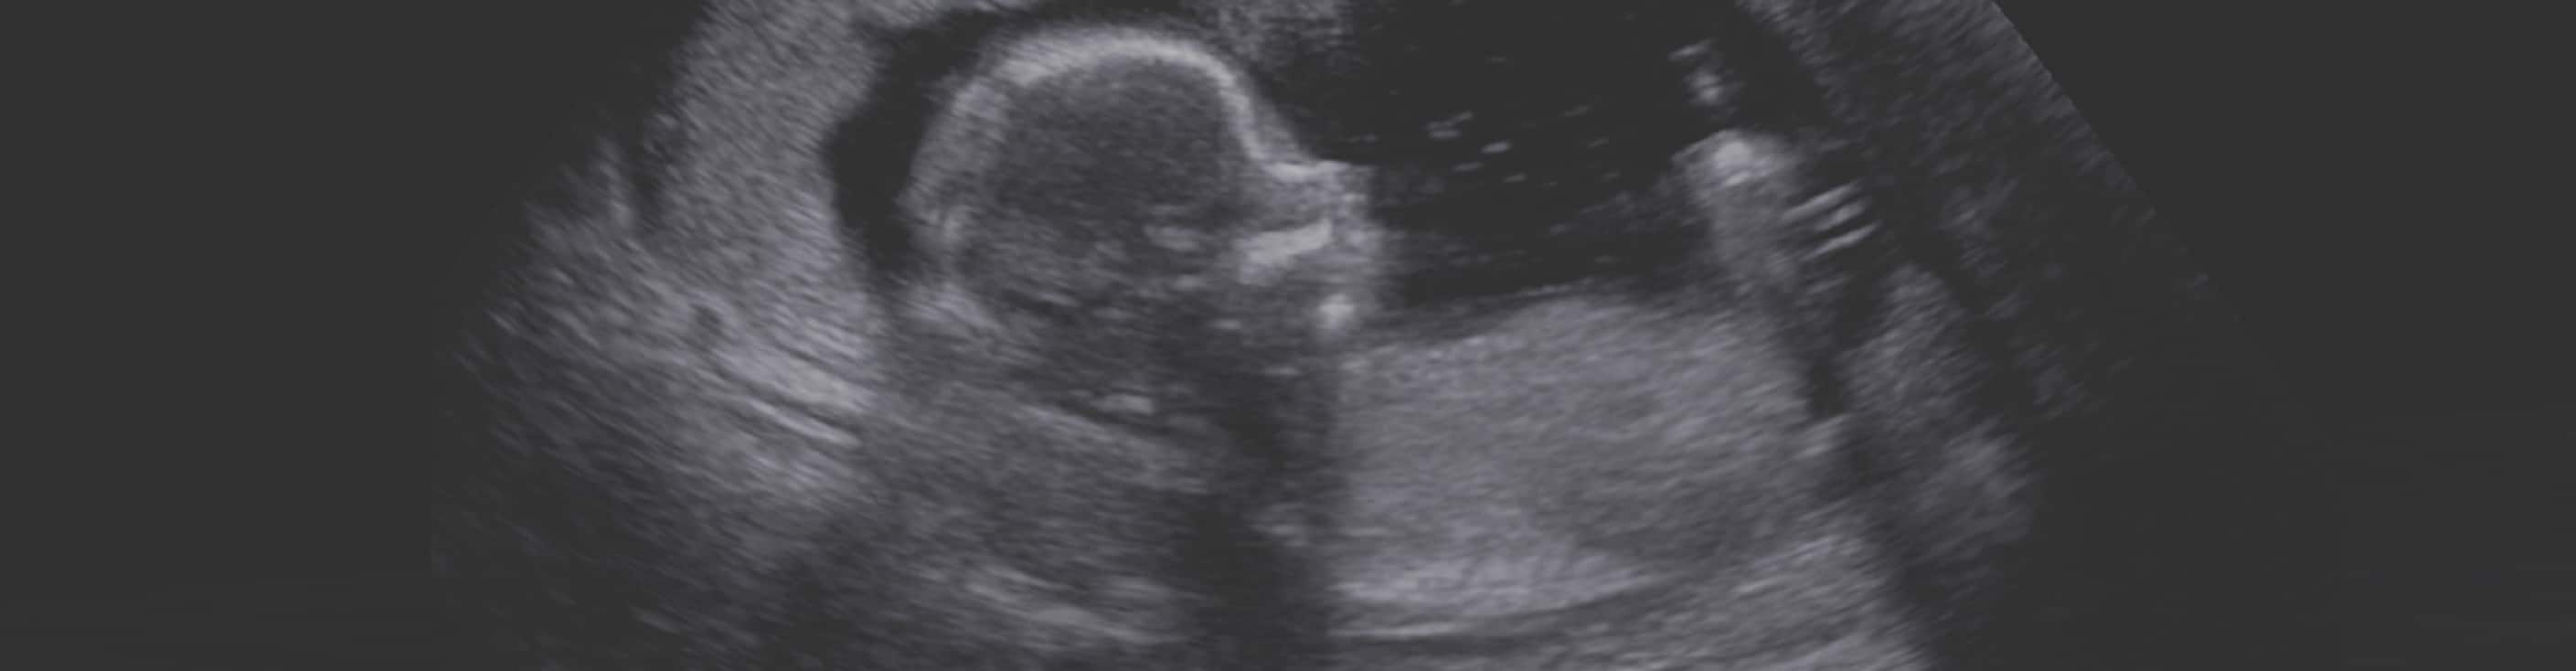

Week 16

The baby has quadrupled in size by now. Fingernails and toenails are also present. She sleeps and wakes regularly and is about 6-8 in. long.